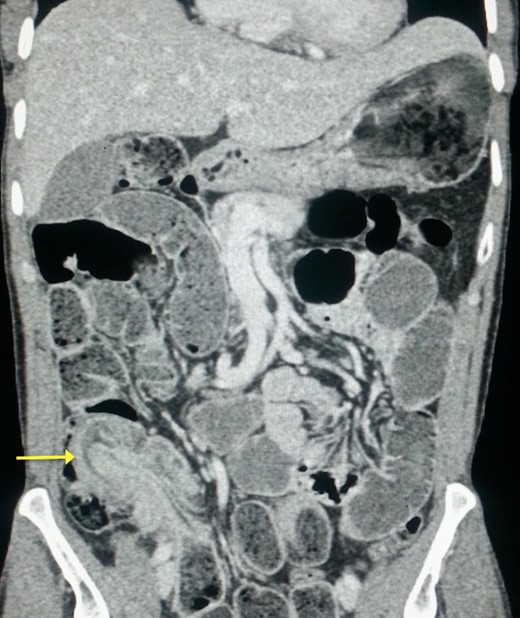

A plain abdominal radiography suggested a bowel obstruction, by showing multiple air-fluid levels. Biological results were the following: hemoglobin: 13,5 g dl−1, hematocrit rate: 42,5%, white blood cell count: 8×103 mm−3, creatinine = 18 mg L−1, serum Na: 139 m Eq L−1, serum K: 3.4 m Eq L−1. The contrast-enhanced CT showed a target mass localized in the right iliac fossa, and was suggestive of ileocecal intussusception without specifying the underlying cause (Fig. 1). While coronal reconstruction showed a « sausage-shaped mass » (Fig. 2). Moreover, there was some lymphadenopathies surrounding the target mass, and a small amount of abdominal effusion.

Coronal reconstruction of abdominal CT showing the ‘sausage sign’ of ileocecal intussusception.

The classic ‘target mass’ picture on CT scan as found in our case, is pathognomonic of intussusception [6]. It consists in a central dense area and a halo of low attenuation being respectively the intussusceptum and the edematous intussuscepiens [7, 8]. In a sagittal view, we found the classical « sausage sign » in our patient. Moreover, CT scan may identify the underlying cause of the intussusception [1]. The common sites of occurrence of this condition are the junction between the movable segments of the intestine and segments that are relatively fixed as in our case.